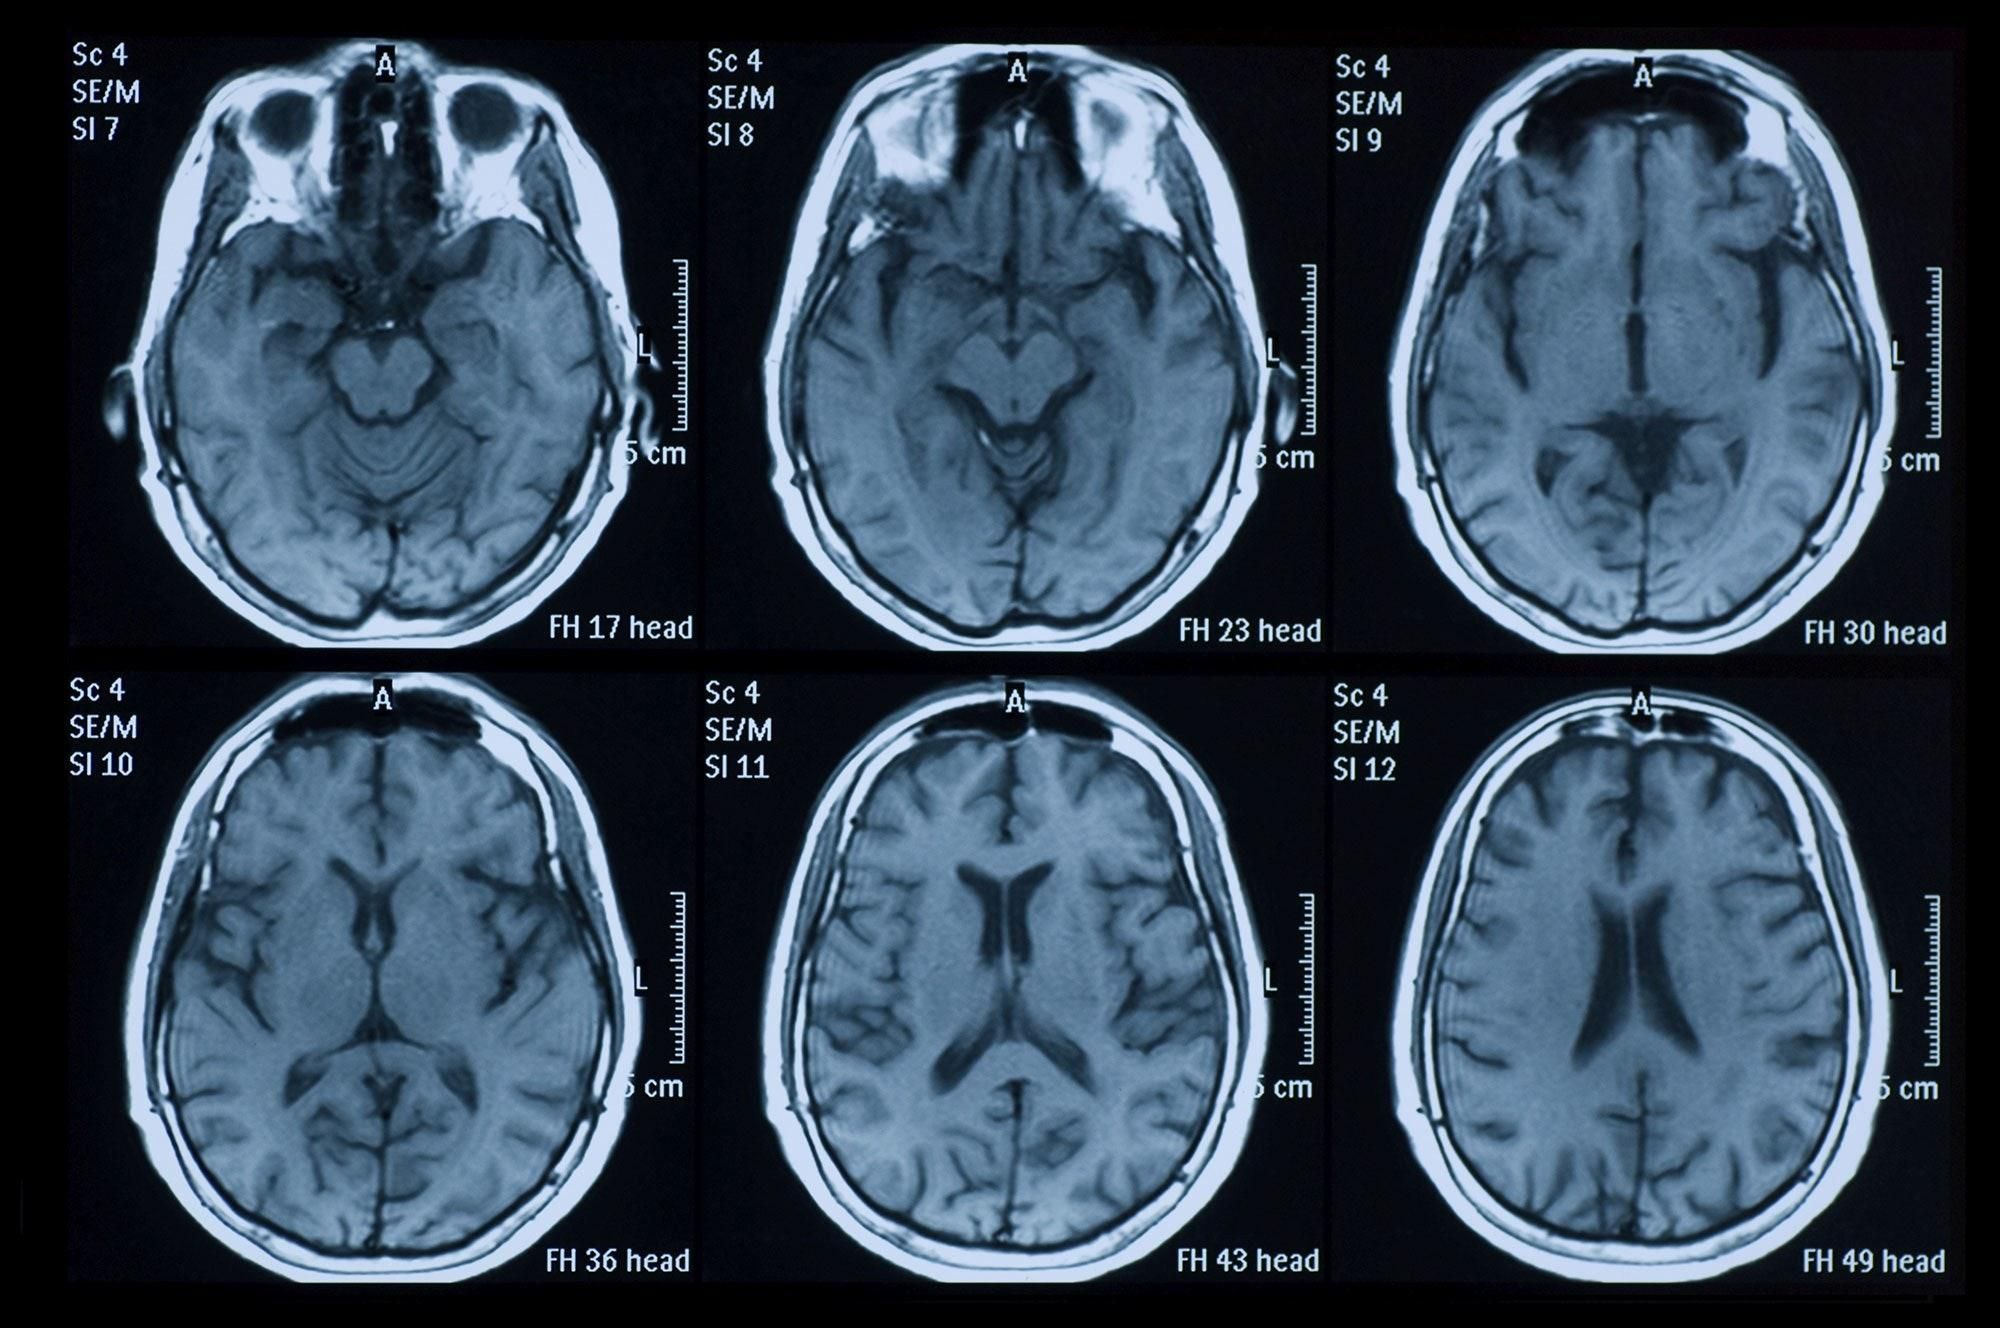

COVID-19 пошкоджує мозок

Повідомляється про 74-річного чоловіка і 58-річну жінку, які захворіли на коронавірус і перенесли неврологічні розлади. Скани мозку жінки продемонстрували зменшення щільності мозкової речовини й кровотечі. При цьому в лікарню її доставили в летаргічному стані, зі сплутаністю свідомості й дезорієнтацією.

Лікарі виявили смерть клітин і кровотечі мозку, у відділах, які відповідають за відчуття, пам'ять, свідомість і передачу сенсорної інформації. Ці пошкодження сталися в результаті набряку мозку – енцефаліту, який також спостерігається у деяких важких хворих на грип та вітрянку.

COVID-19 викликає кровотечі в мозку / unsplash.com

Поки що серед мільйона пацієнтів з коронавірусом лише дуже невелика кількість має неврологічні ускладнення. Але скільки їх насправді наразі невідомо, тому що сканування мозку всім пацієнтам не проводяться, і в стандартний протокол вони не включені.